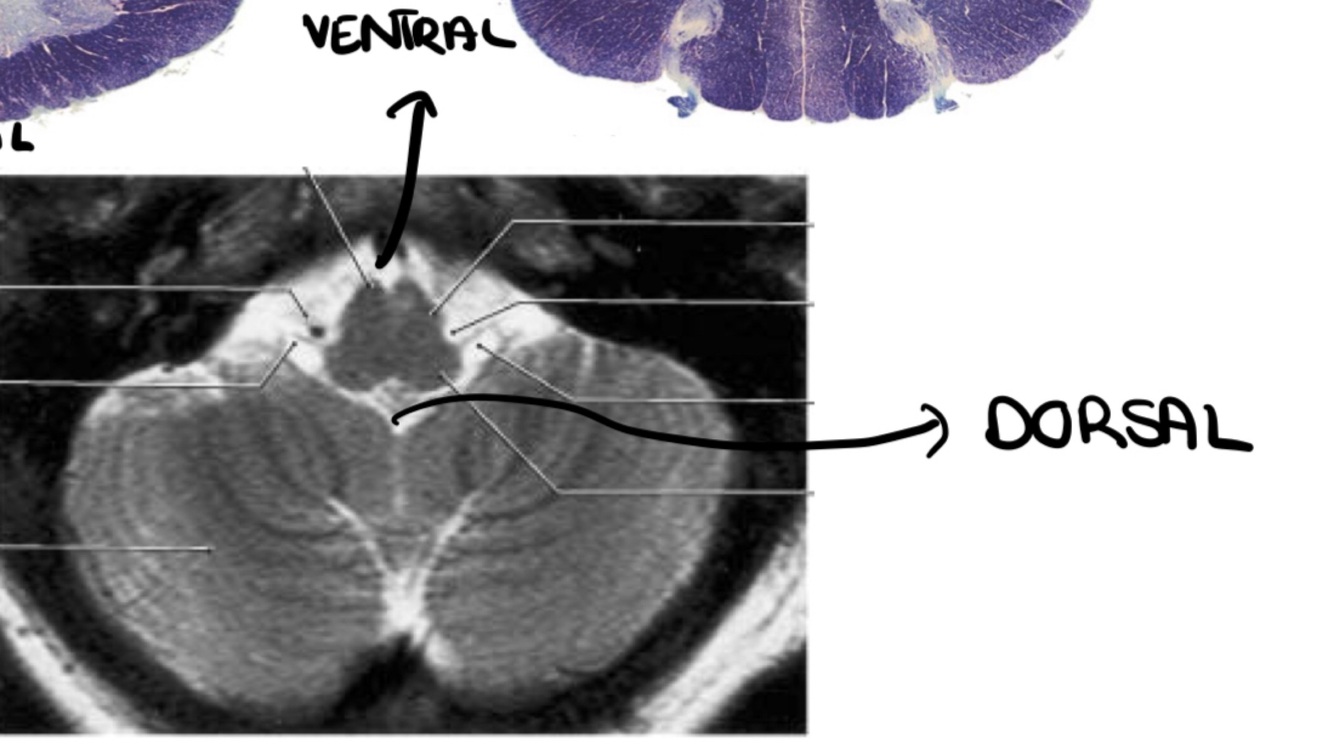

Q

Which type of orientation is this one?

A

Anatomical

Clinical